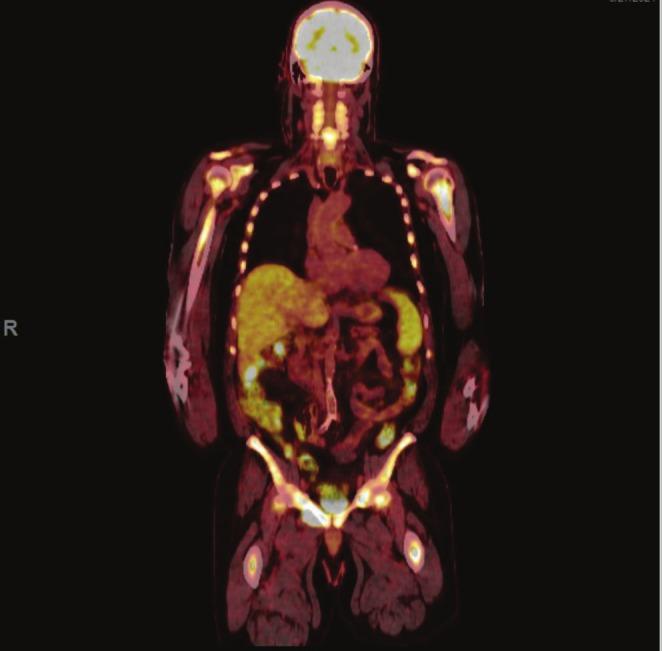

Here, we present a case of multifocal secondary colonic EMP in a patient with relapsed refractory multiple myeloma (RRMM) and review literature demonstrating other cases of secondary colonic EMP.

在此,我们报告一例复发难治性多发性骨髓瘤(RRMM)患者发生多灶性继发性结肠EMP的病例,并回顾文献中显示的其他继发性结肠EMP病例。